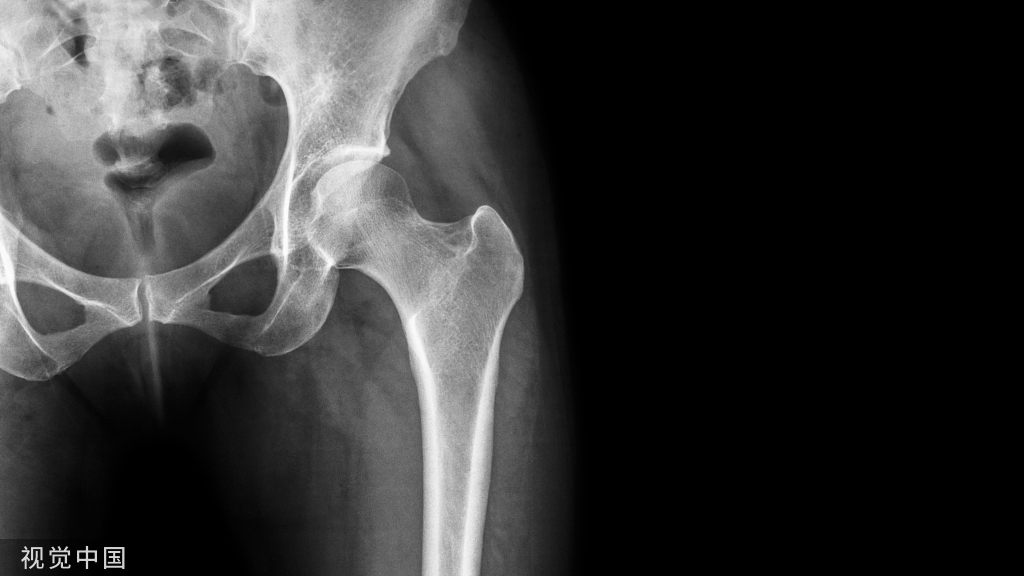

平片一

X 线平片上表现为伴有清晰薄层硬化缘的环形(囊状)透亮区,CT 上表现为圆形 或类圆形的皮质下局灶性骨质缺损,周围见薄层硬化带环绕 边缘锐利,部分较大病灶在病灶层面或上下相邻 、层面上前方显示皮质与病灶相通的局部裂隙样缺损病灶,最大径线通常小于 10 mm;MRI 示病灶在 T1WI 上呈低信号,在 T2WI 上呈均匀或不均匀高信号。